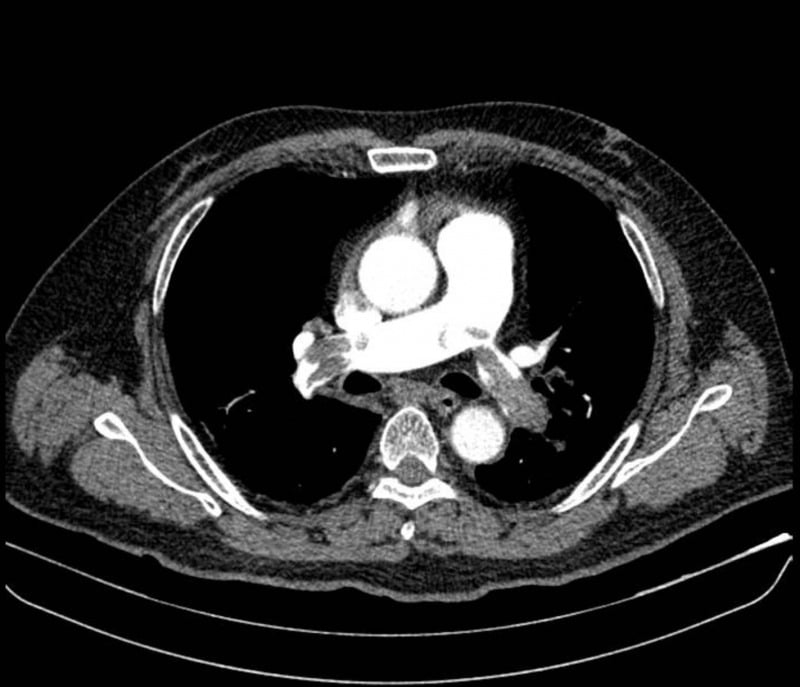

فرنٹ لائن پر، اسے مشتبہ مایوکارڈیل انفکشن کی تشخیص ہوئی اور اسے فوری طور پر دوسرے ہسپتال منتقل کر دیا گیا۔ پیپلز ہسپتال 115 میں پلمونری خون کی نالیوں کے سی ٹی اسکین سے شدید پلمونری ایمبولیزم کا انکشاف ہوا، جس میں خون کے بڑے جمنے دونوں پلمونری شریانوں میں رکاوٹ بنتے ہیں، جس سے روکنے والے صدمے ہوتے ہیں۔ مریض کا علاج تھرومبولیٹک ادویات سے کیا گیا اور ایک ہفتے کے بعد صحت یاب ہو گیا۔

لوئر ایکسٹریمیٹی ویسکولر الٹراساؤنڈ نے بائیں فیمورل اور پوپلائٹل رگوں میں تھرومبوسس کا انکشاف کیا۔ ڈاکٹروں نے تعین کیا کہ اس کی وجہ مریض کی 20 سال سے زیادہ کی سگریٹ نوشی کی عادت سے ہے، جس میں تمباکو نوشی کی سطح تقریباً ایک پیکٹ فی دن تھی۔